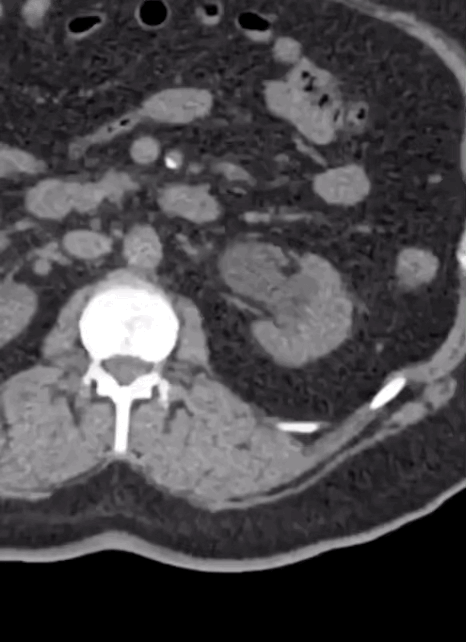

Case 6

A male in his 30s presents with abdominal pain. Here is a non contrast CT of his abdomen and pelvis.

Tap the first icon on the left to scroll.

What best describes the main scan finding? Choose one from the following options: